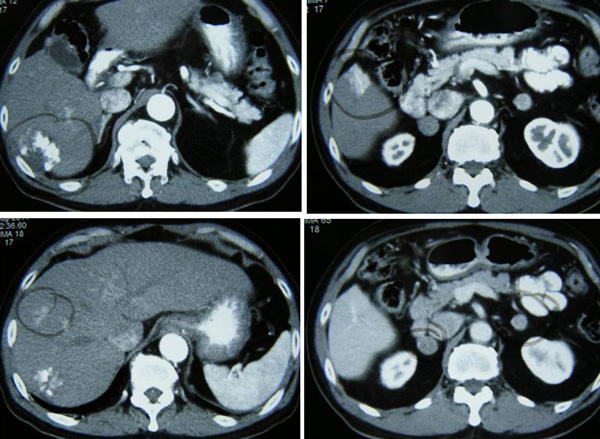

CT scan on 2 June 2010 showed a solitary mass in segments 6 and 7 in the right lobe of his liver, It  measures 7.8 x 6.5 x 8.4 cm. This is compatible with a hepatoma. There is no involvement of the hepatic or portal veins. There is no definite extension beyond the liver capsule. No enlarge lymph nodes were seen in the para-aortic or portahepatis region.

After two cycles of TACE, CT scan on 5 August 2010 showed the tumour has shrunk. The entire mass now measures 6.2 x 4.5 x 5.5 cm. The response was good with no evidence of metastasis.

CT scan on 6 October 2010 showed the tumour was significantly smaller in size, 4.7 x 5.4 x 4.6 cm. There was no evidence of recurrent or new lesions in the rest of the liver. No evidence of pulmonary metastataic deposits and no enlarged mediastinal or lymph nodes.

On 6 April 2011, a CT scan was performed. The previously treated mass in the right lobe of his liver measures approximately 3.5 x 5.1 x 4.8 cm in size. There is no associated hypervascularity seen with this mass. However, there is a new lesion in segment 5 of the right lobe of his liver. It is 3.1 x 2.3 x 3.6 in size.  This mass was not present on the previous scan of October 2010 and is suspicious of recurrent disease.

TD came to a private hospital in Penang and underwent a CT scan of his brain, neck, thorax, abdomen and pelvis on 12 August 2011. The results showed:

1. There is a 5.1 x 4.2 x 4.8 cm mass in segment 6 of the liver.

2. There is a 2.7 x 2.8 x 3.3 cm enhancing lesion in segment 5 of the liver.

3. There is an ill-defined enhancing lesion measuring about 2.3 cm in segment 8 of the liver.

4. There is a 2.5 x 2 x 2.1 cm mass just inferior to the right adrenal gland. Metastasis?

5. There is a 1.9 x 1.6 x 2.5 cm mass just inferior to the left adrenal gland. Metastasis?

6. There is a lytic lesion in the vertebral body of T12. Fracture of the superior endplate of T12 is noted. This probably represents a bony metastasis.